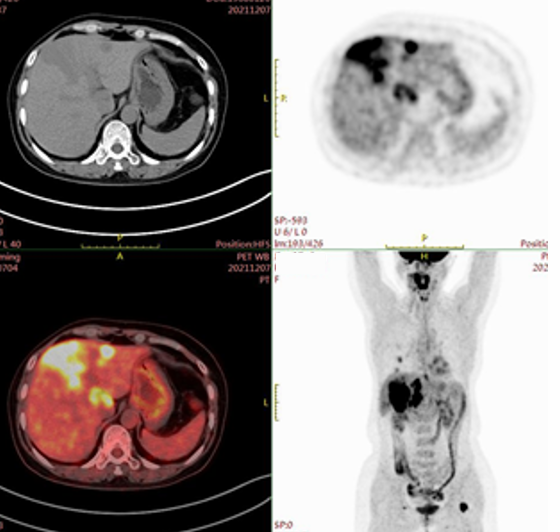

复发转移:2021年12月1日复查;腹部超声:肝脏实质内见多个大小不等的低回声团,较大的约46 mm×44 mm;余实质回声均匀。肿瘤标志物:CEA 8.63 ng/mL(参考范围0~5 ng/mL),CA15-3>300 U/mL (参考范围0~25 U/mL) 。2021年12月7日PET-CT肝脏多发转移灶,较大者较大截面约5.7×6.9 cm,边界欠清,FDG代谢增高,SUVmax=14.0;左侧股骨上端转移灶。2021年12月10日超声引导下行肝脏占位穿刺病理:肝脏组织中见中-低分化腺癌,结合免疫组化标记结果考虑为乳腺癌转移;免疫组化结果显示癌细胞C-erbB-2(3+),ER(1+,约20%),PR(-),Ki-67(+,约40%)。

图1.PET-CT